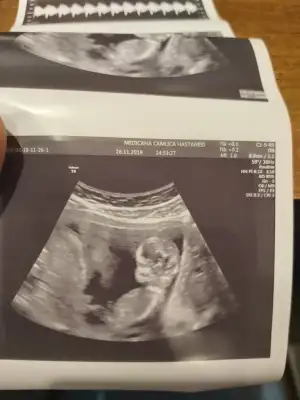

Erkek mi ki acabaTeyzeler bu da bizim fotomuz ☺

Kız gb sanki ya ben hıc anlamam daNub ne kızlar ben bilmiyorum bende attım banada tahmin edin kim anlıyorsa size el salladık hatta aşk olsun kızlar![]()